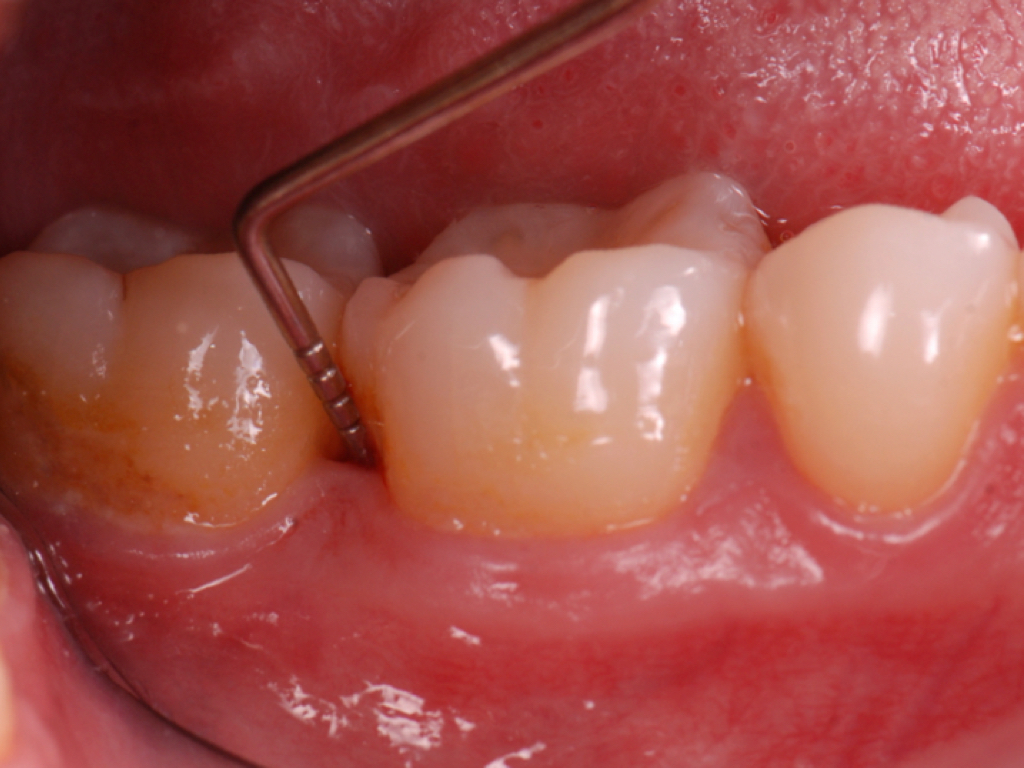

Fig 1. Inaccurate probing angle wrongly indicates probing depth at 3 mm, which does not correspond to the radiographic finding shown in Fig 2.

Figure 1

Fig 3. Correct angulation of the probe demonstrates 6-mm probing depth.

Figure 3

Clinical PPD is measured to the nearest millimeter by means of a graduated periodontal probe with a standardized tip diameter of approximately 0.4 mm to 0.5 mm. Several factors can influence the measurements made with periodontal probes, including: the thickness of the probe used5; the angulation and positioning of the probe depending on anatomic features, such as the contour of the tooth surface (Figure 1 through Figure 3)6; the graduation scale of the probe5; the pressure applied on the instrument during probing6; and the degree of inflammatory cell infiltration in the soft tissue and accompanying loss of collagen.7